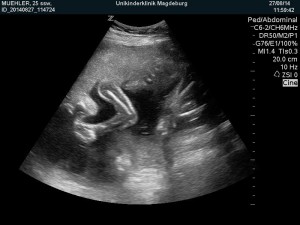

Heute gab es ein Fotoshooting der besonderen Art beim Opa auf Arbeit. Sein Kollege, der stellvertretende Chefarzt der Kinderklinik und gleichzeitig Guru des Ultraschalls, hatte sich bereit erklärt den werdenden Eltern noch ein paar aktuelle Fotos zu machen. Leider gab es kein 3D, aber dafür ein paar süße Fotos und vor allem Videos unseres Sohnemannes, der sich die ganze Zeit über ruhig verhielt und sich der Kamera, äh dem Schallkopf stellte.